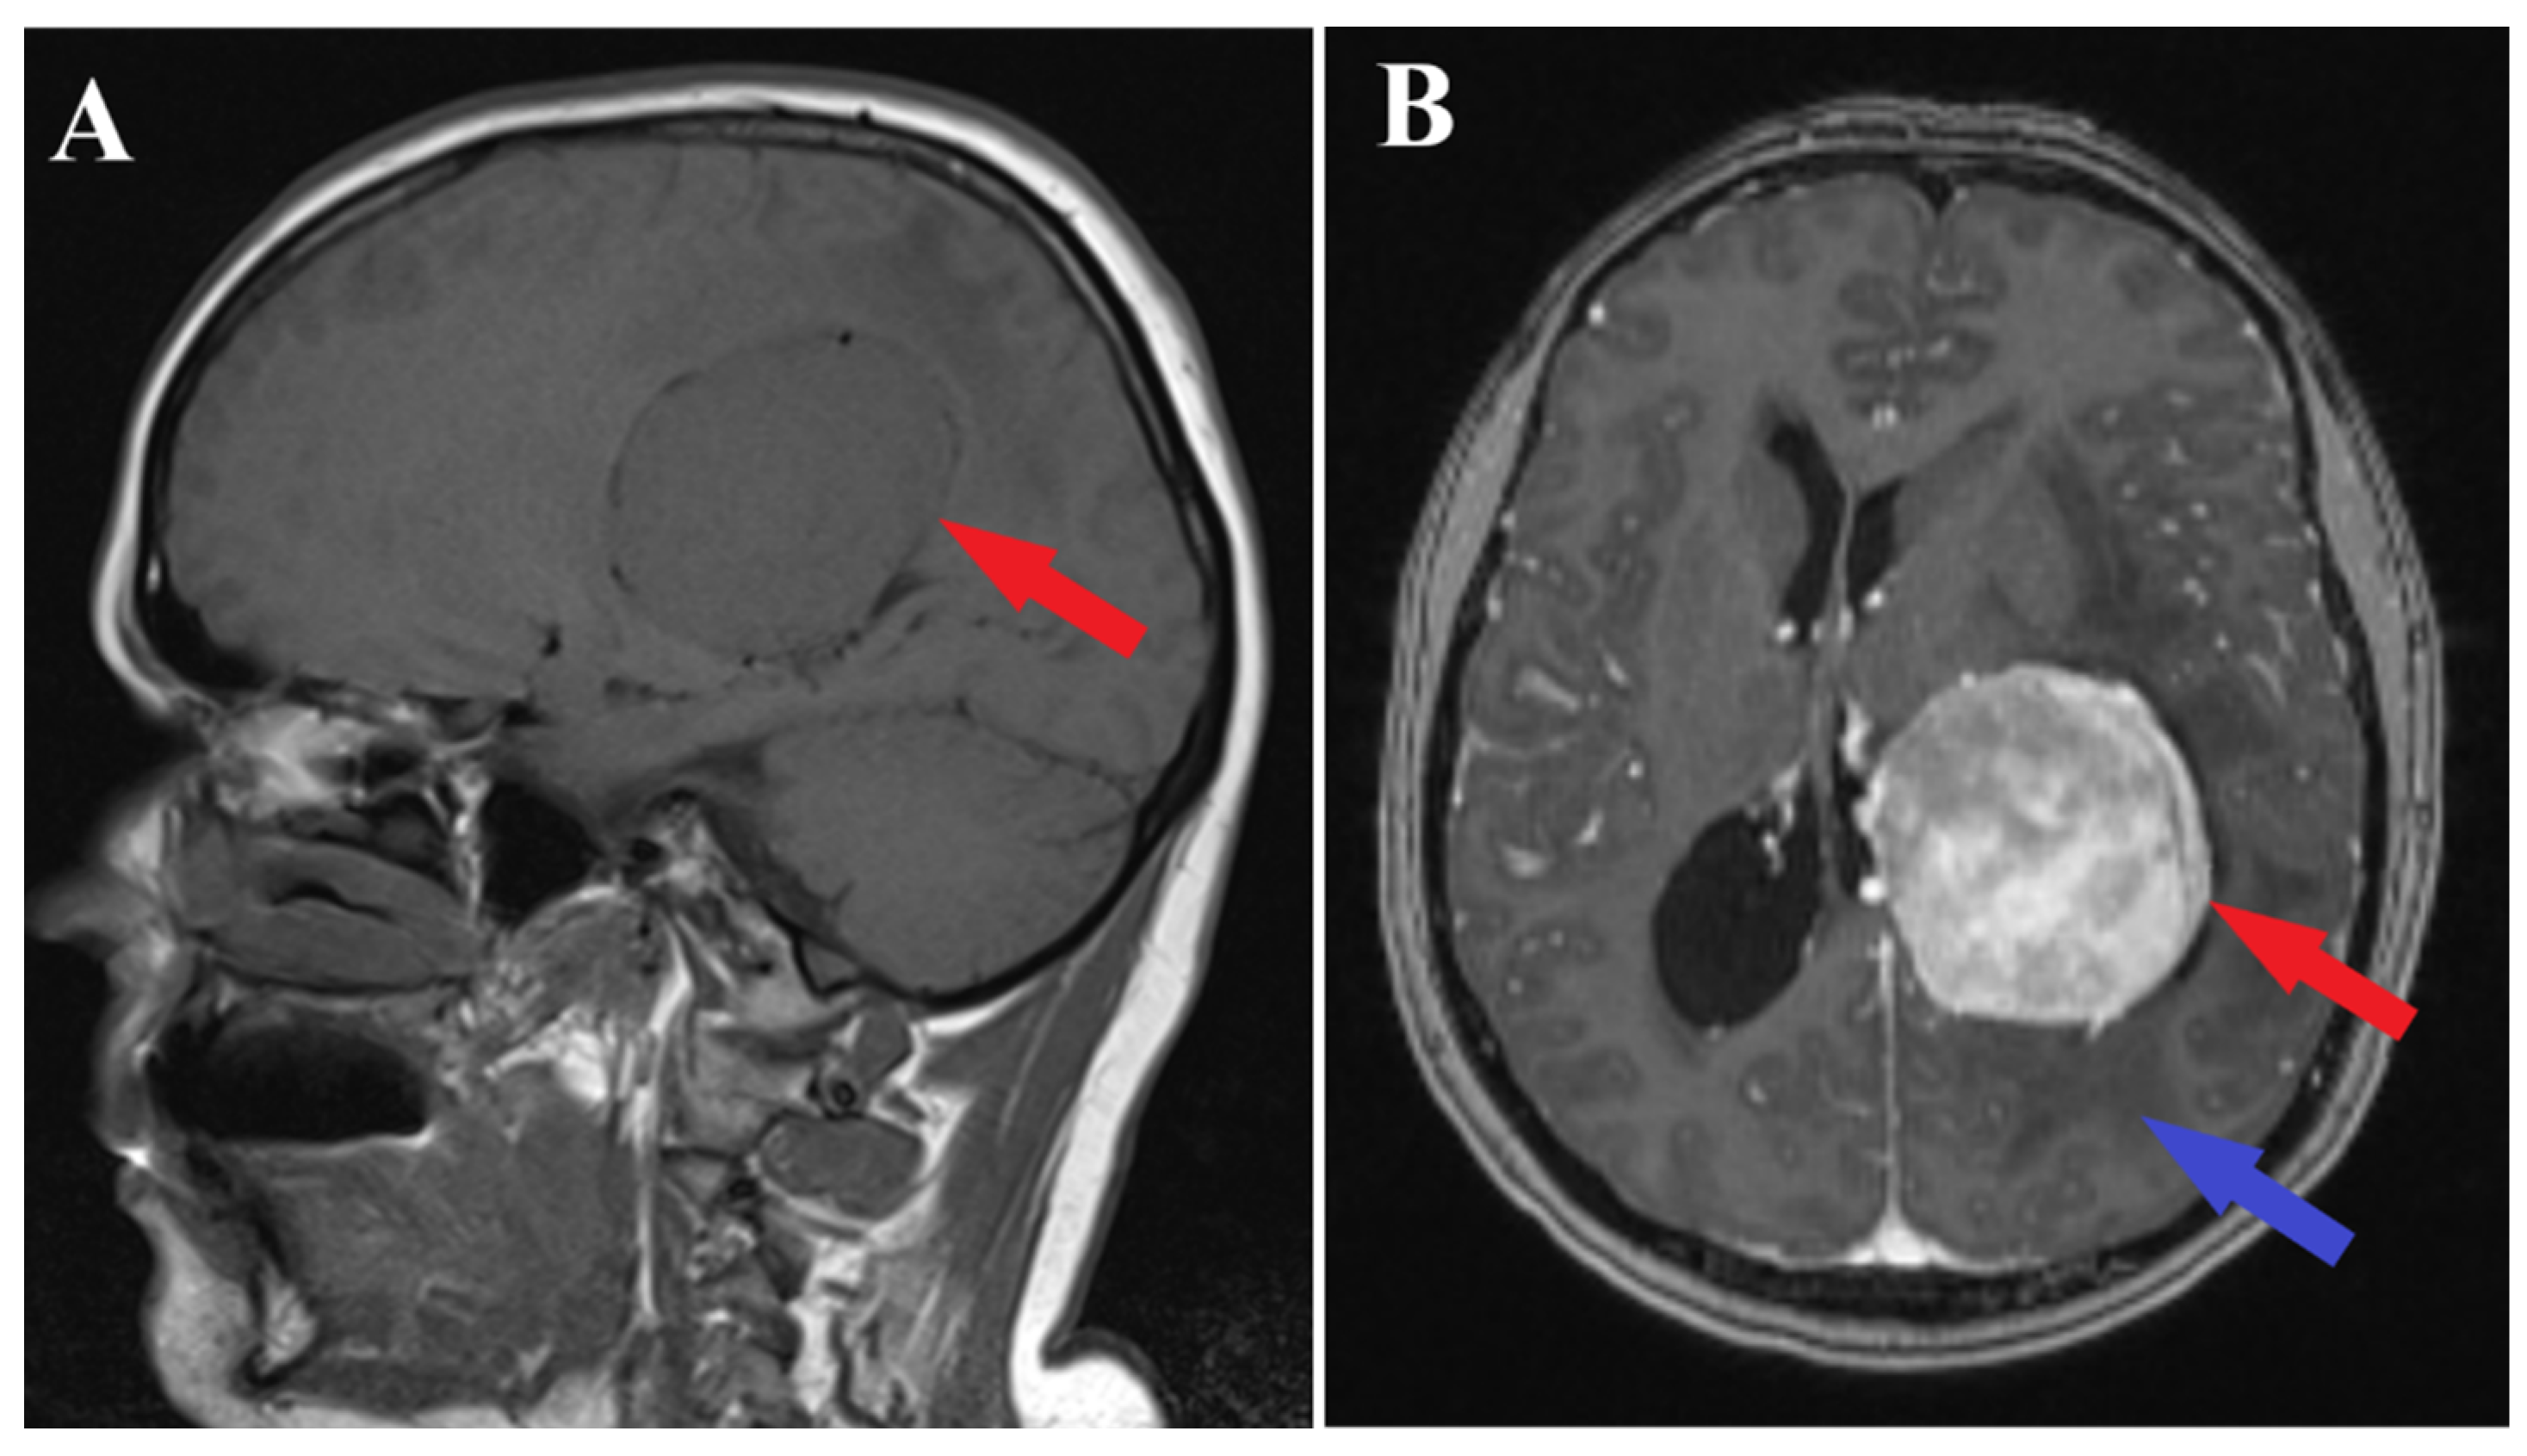

A brain MRI (i.e., multi-planar, multi-sequential brain MRI examination was performed on a General Electric 3T Signa Architect, Chicago, IL, USA) with contrast enhancement revealed an intraventricular tumor located in the body of the left lateral ventricle. The tumor presented as an ovoid, well-delineated mass with T1 hypointensity and T2 hyperintensity, measuring up to 60 mm in maximum diameter. It induced deformation of the left lateral ventricle. The tumor was associated with substantial digitiform edema, causing a shift in the midline structures and a potential risk of subfalcine herniation (Figure 1 and Figure 2).

Figure 1.

Preoperative MRI T1 and T1Gd sequence. Sagittal section of MRI T1 sequence (A) and axial section of MRI T1 Gd sequence (B), depicts an intraventricular mass into the left ventricle body (red arrows) with associated perilesional edema (blue arrow).